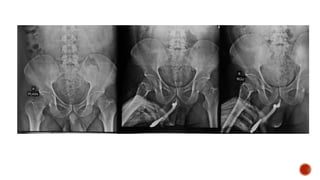

 Parts of male urethra

 Plain film :

 causes of stricture-

 pelvic trauma(pelvic bone fractrues)

 spinal cord injury(lumbar spine fracture)

 prostatic carcinoma mets to bones(stricture at prostatic level)